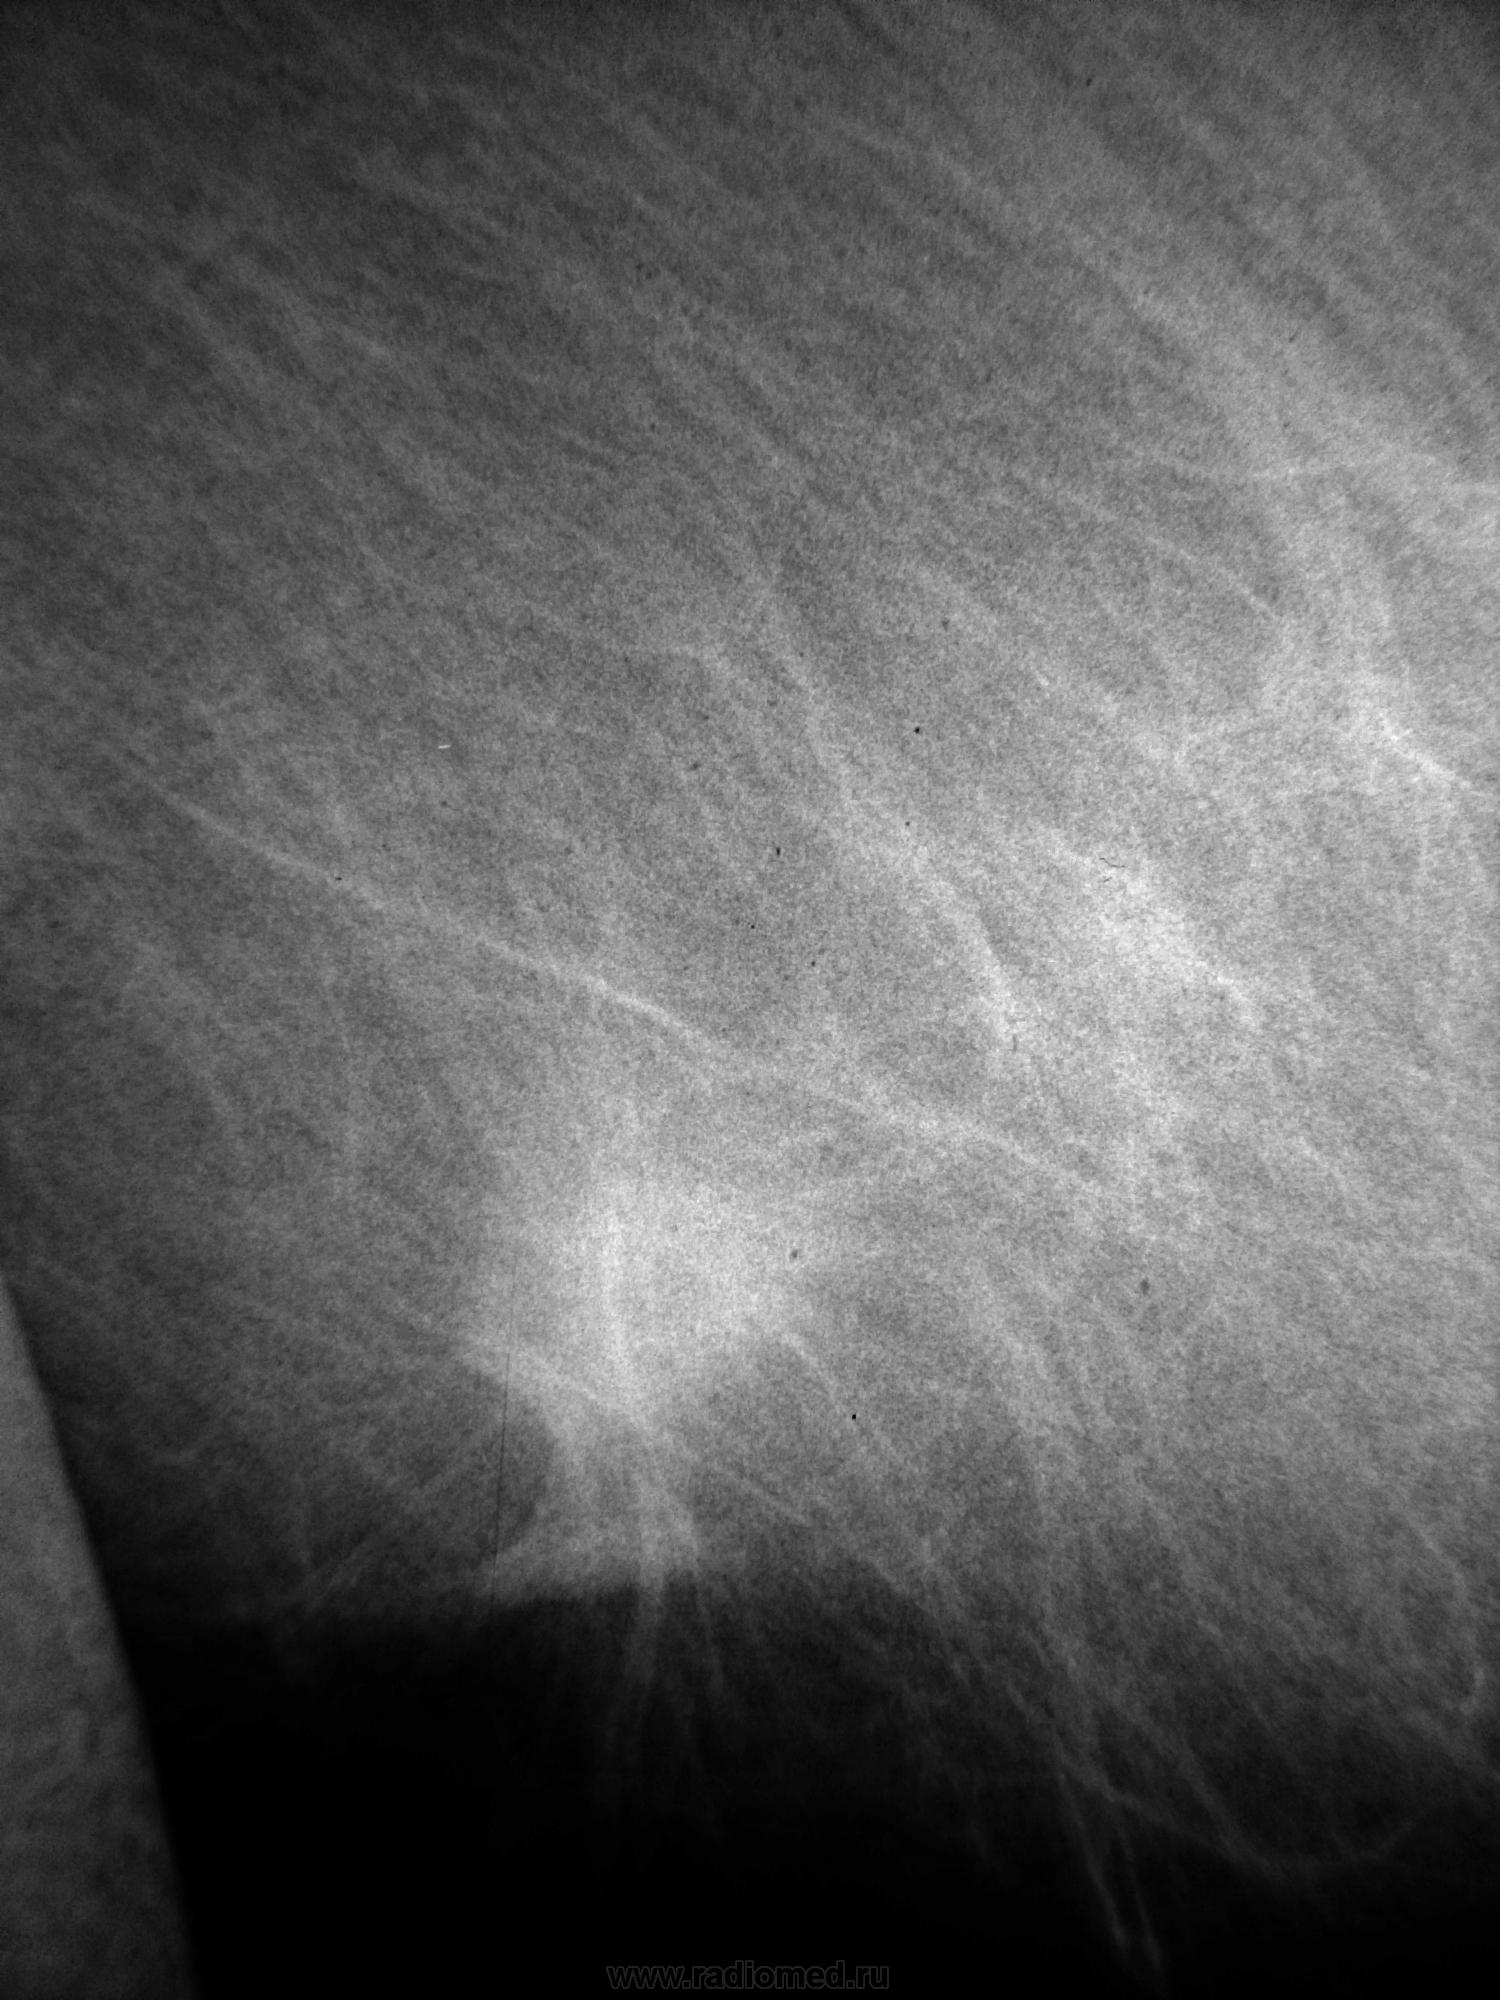

Женщина 55 лет. Самообращение. Вот такая шишечка, спаяна с кожей (симптом площадки и лимонной корки до 1.5 см в диаметре). Обследуется впервые. Направлена к онкологу.

Во-первых, это не инфильтративный рак, а классический узловой, с вовлечением кожи, т.к. близко к ней. Если присмотреться, видны держалки негатоскопа - это пленки. Аппарат Giotto (Италия), пленка маммографическая Kodak. Фото с негатоскопа, оцифровка в Фото эдитор онлайн.

Классическая картина, хоть в учебник.

Думаю, что коллега хотел сказать, что это не отёчно-инфильтративная форма рака, а узловая с инфильтративным ростом.

Слева подмышечный лимфоузел 3.5х2.5 см (край его виден на снимке).